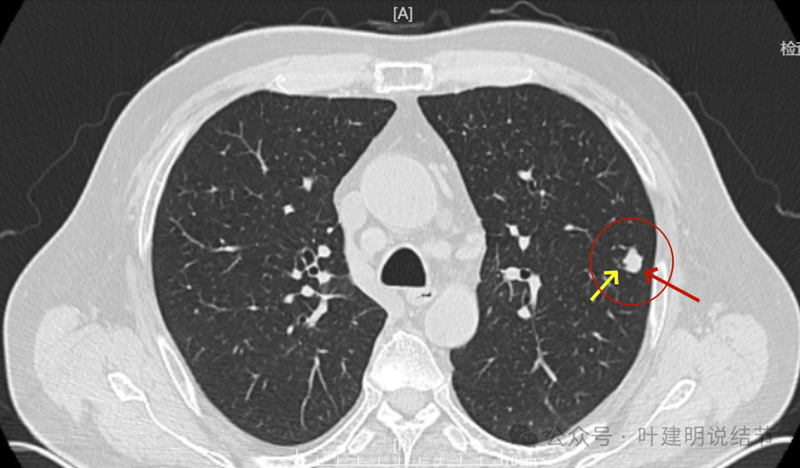

2024年5月病灶又有增大进展,实性密度,轮廓较清。

2024年9月再增大进展,见血管进入明显,靠血管这侧的边缘较为毛糙。

局部放大病灶表面不平,血管进入,进入的血管有异常增粗,没有见到明显卫星病灶。